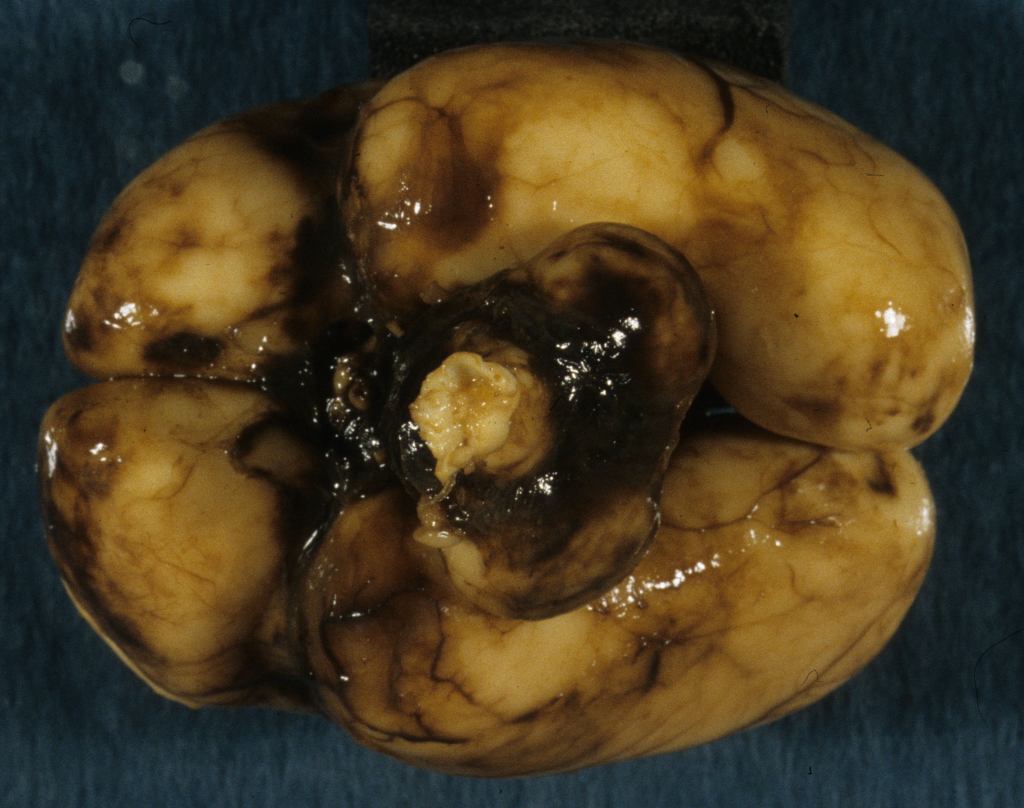

Parenchymal hemorrhage:

Deep hemorrhages may be evident in the intact brain if the hemorrhage extends to the subarachnoid surface (Fig 6a, b).

The causes of such hemorrhage may be from vascular malformation such as Vein of Galen aneurysm or from thrombocytopenia especially with anti- platelet antibody A1 in the mother3,4. As with Rh disease, the fetus must be A1 positive in an A1 negative mother. Infarctions of the brain may appear hemorrhagic. Because of the large proportion of spinal fluid and the flexible skull with unfused sutures, hemorrhage into the brain can cause fetal anemia and hemorrhage shock (Fig 7a, b, c).